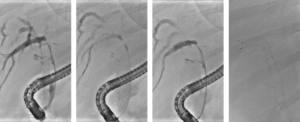

Een 68-jarige vrouw werd verwezen in verband met verdenking op een perihilair cholangiocarcinoom, Bismuth type IIIb (figuur 1). In verband met icterus en mogelijke hemihepatectomie links werd er een plastic endoprothese in de rechter ductus hepaticus geplaatst. De galwegen links werden bewust niet gecontrasteerd. Tevens werd een brush afgenomen die de diagnose adenocarcinoom bevestigde. Vanwege snel toegenomen vaatbetrokkenheid kwam patiënte niet meer in aanmerking voor resectie of levertransplantatie. Derhalve werd gestart met palliatieve systeemtherapie en werd de plastic stent electief gewisseld voor een ‘uncovered’ metalen stent (uSEMS). Aangezien er, op basis van het lage bilirubinegehalte (11 μmol/L), reeds voldoende drainage met een unilaterale stent was bereikt, werd er niet aanvullend bilateraal gedraineerd. In studieverband (RACCOON-pilot [NL9144]) werd de stenose geableerd met endobiliaire radiofrequente ablatie (eRFA), met het doel om de duur van de stentdoorgankelijkheid te verlengen. Met een 22 mm ELRA-electrode (Taewoong Medical) werd de stenose 90 seconde geableerd met 7 watt en target temperatuur van 75 graden (figuur 2). De ductus cysticus werd niet in het traject betrokken om een post-procedurele cholecystitis te voorkomen. Na verwijderen van necrotisch materiaal met een extractieballon werd een 80 x 8 mm uSEMS geplaatst (figuur 3). 5 maanden later ontwikkelde patiënte klachten passend bij stentobstructie. Er werd opnieuw eRFA verricht van de stenose in de stent en een tweede 60 x 8 mm uSEMS in de reeds aanwezige stent geplaatst (figuur 4). Weer 5 maanden later ontwikkelde patiënte recidiverende klachten. Er werd opnieuw eRFA verricht, maar ditmaal werd geen aanvullende stent geplaatst (figuur 5). Patiënte overleed 5 maanden later zonder terugkerende obstructie, 2 jaar na de diagnose.

RFA ter palliatie van hilaire maligne stenoses is samen met uncovered metalen stents waarschijnlijk de beste weg naar optimale palliatie. Initieel starten we meestal met plastic stents om zeker te weten dat de gedraineerde systemen adequaat zijn voor palliatie van de icterus zonder cholangitis. Direct starten met metalen stents heeft als risico dat bij onvoldoende drainage additionele segmenten door de metalen stents moeilijk te benaderen zullen zijn. De ‘test-palliatie’ met plastic stents ondervangt dit probleem. Zodra aldus palliatie is gegarandeerd, is transitie naar metalen stents een logische stap omdat deze langer patent blijven en geen andere segmentele takken afsluiten. Bij obstructie van deze stents is RFA een goede optie om stents weer open te maken en re-interventies te voorkomen. Figuur 3 toont op de derde foto van links evidente verbetering van de stenose na RFA en verwijdering van het necrotische tumor debris.